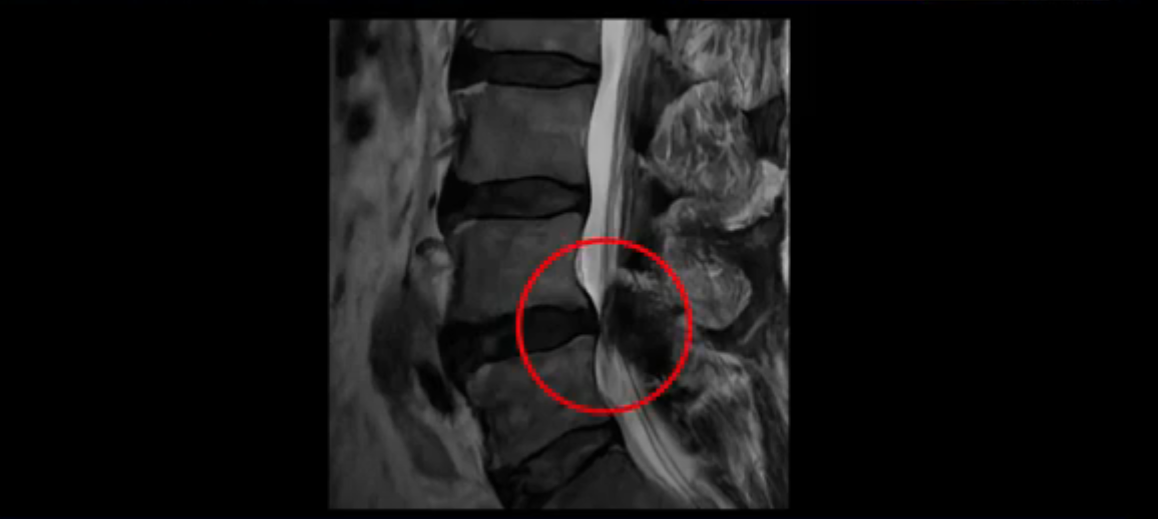

이분은 협착증 환자입니다. 이분 MRI 보면서 상태를 설명해 드린 후 어떻게 협착증이 수술 없이 치료가 가능한지 설명해 드리도록 하겠습니다. 이분 MRI에 보시면 4번, 5번 마디의 중심성 협착증이 있습니다.

뒤에 있는 후관절과 황색인대가 두꺼워져서 척추관이 많이 좁아져 있습니다.

여기서 신경 눌림 증상이 발생했을 가능성이 높습니다. 이런 환자들이 수술 없이도 치료가 가능한 이유는 협착증은 신경 구멍이 좁아져서만 생기는 것이 아니고 나이 들면서 근육이 동시에 나빠졌을 때 협착증 증상이 발생하기 때문입니다. 협착증은 노화와 퇴행으로 척추의 신경 구멍이 좁아지고 동시에 근육이 줄어들고 약해지면서 문제가 생기니까 허리를 잘 지탱하지 못하고 그래서 신경이 눌리는 겁니다. 즉 약해져서 뭉치고 뒤틀린 근육을 근육재활치료로 잘 치료해서 근육이 좋아지면 협착증 증상이 좋아지는 겁니다. 즉 근육이 줄어들고 약해지고 뭉치고 뒤틀릴 때 신경 눌림 증상이 생기니까 근육재활치료로 근육만 좋아져도 협착증 증상이 좋아지기 때문입니다.